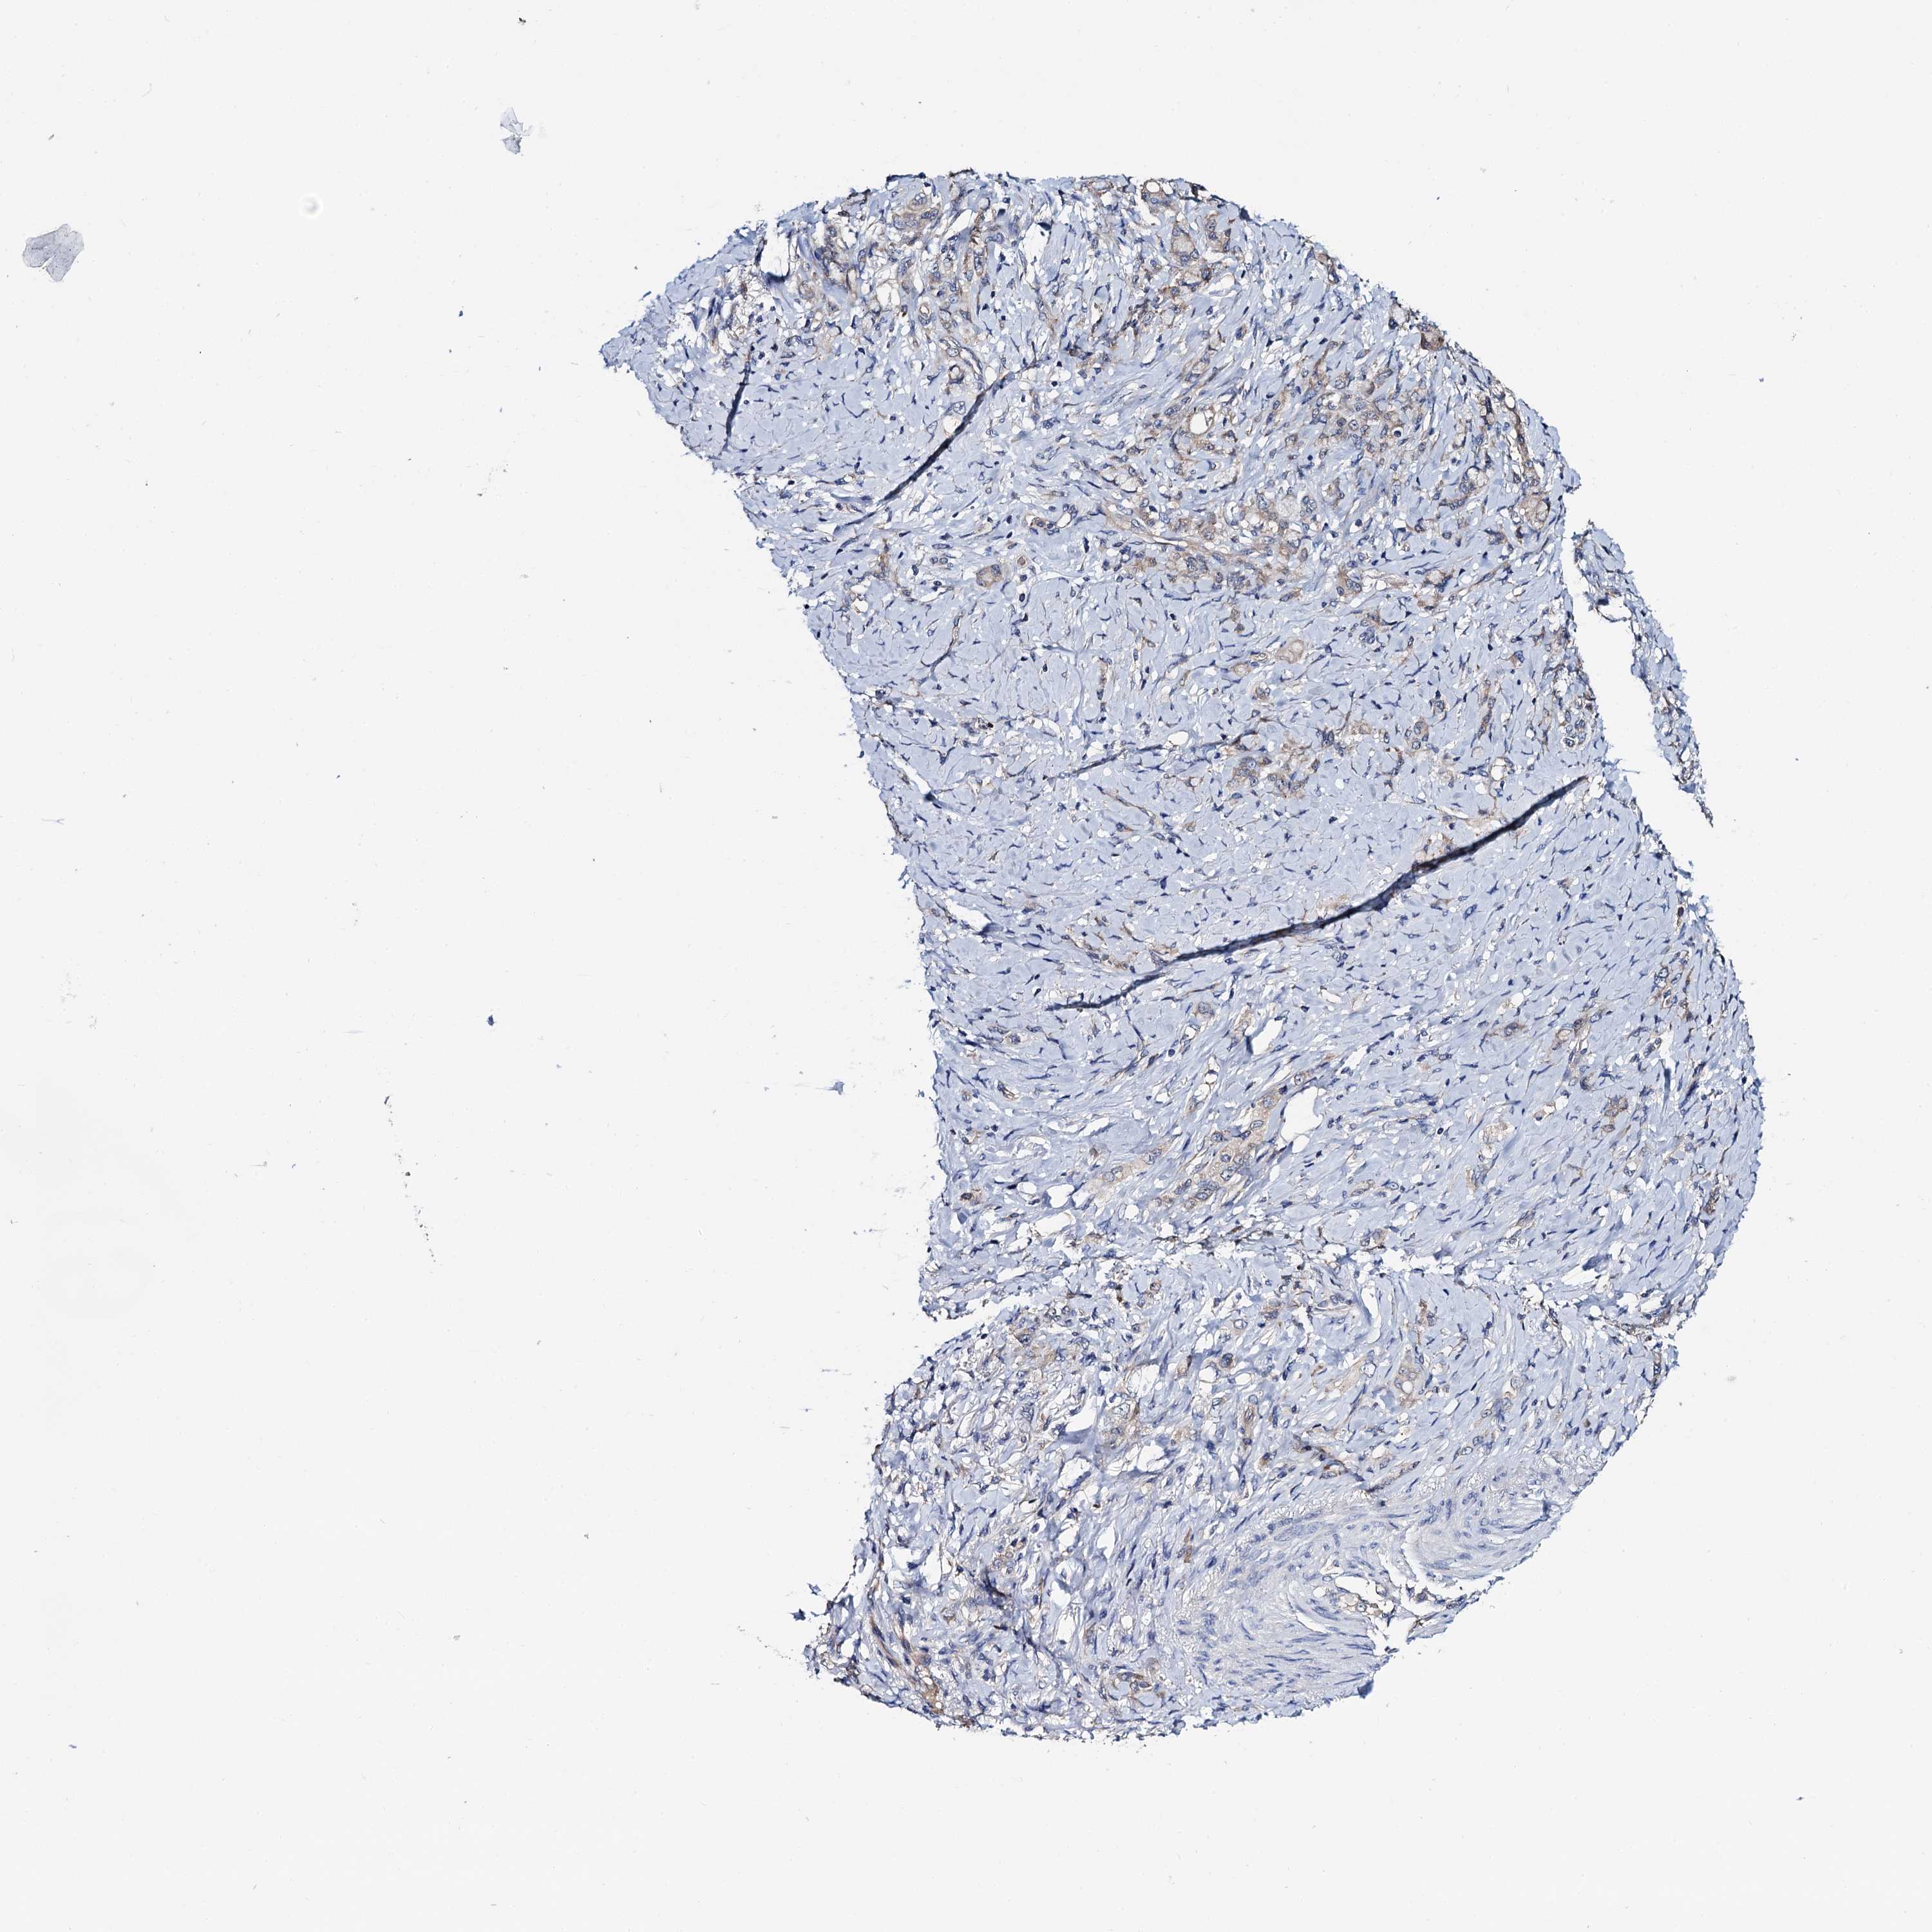

STOMACH CANCER - Protein expressioni

A mouse-over function shows sample information and annotation data. Click on an image to view it in a full screen mode. Samples can be filtered based on level of antibody staining by selecting one or several of the following categories: high, medium, low and not detected. The assay and annotation is described here.

Note that samples used for immunohistochemistry by the Human Protein Atlas do not correspond to samples in the TCGA dataset.

Antibody stainingi

Antibody staining in the annotated cell types in the current human tissue is reported as not detected, low, medium, or high, based on conventional immunohistochemistry profiling in selected tissues. This score is based on the combination of the staining intensity and fraction of stained cells.

Each image is clickable and will lead to virtual microscopy that enables deeper exploration of all samples and also displays staining intensity scores, fraction scores and subcellular localization as well as patient and tissue information for each sample.

Antibody HPA039901

Antibody HPA040006

Staining

High

Medium

Low

Not detected

Intensity

Strong

Moderate

Weak

Negative

Quantity

>75%

75%-25%

<25%

None

Location

Nuclear

Cytoplasmic/membranous

Cytoplasmic/membranous,nuclear

Adenocarcinoma, NOS

Adenocarcinoma, High grade